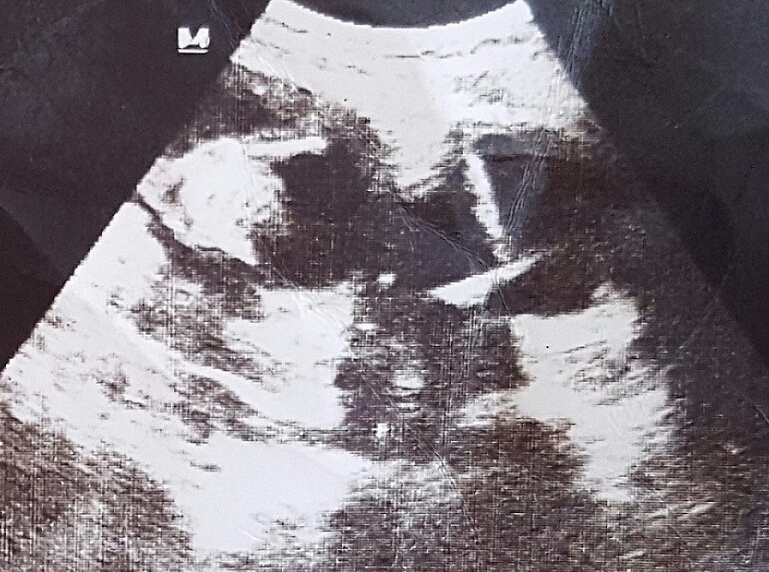

haftasında ortaya çıktığı öğrenildi. Hastanın yapılan obstetrik ultrasonografisinde

tek canlı 15 hafta ile uyumlu gebelik ve mesane lümeninde RİA ekosu izlendi. RİA

complaints that emerged earlier in her fourth pregnancy. A single live fetus

compatible with 15 weeks and echoes caused by a IUD in the bladder lumen were

observed during the obstetric ultrasonography of the patient. IUD was removed